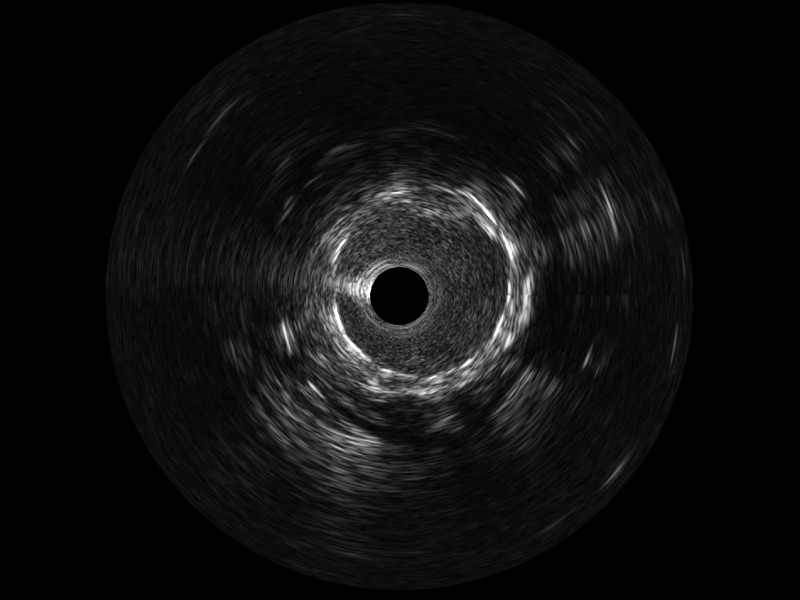

米兰官方网站宽频IVUS图像

传统IVUS图像

对比传统IVUS导管成像,米兰官方网站宽频IVUS图像的近场支架梁显影更细腻,远场中膜外血管仍清晰可辨,兼顾远中近,兼顾分辨力与穿透深度